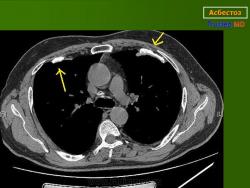

Асбест 1 КТ

Дата: 06/02/2004

Просмотров: 553